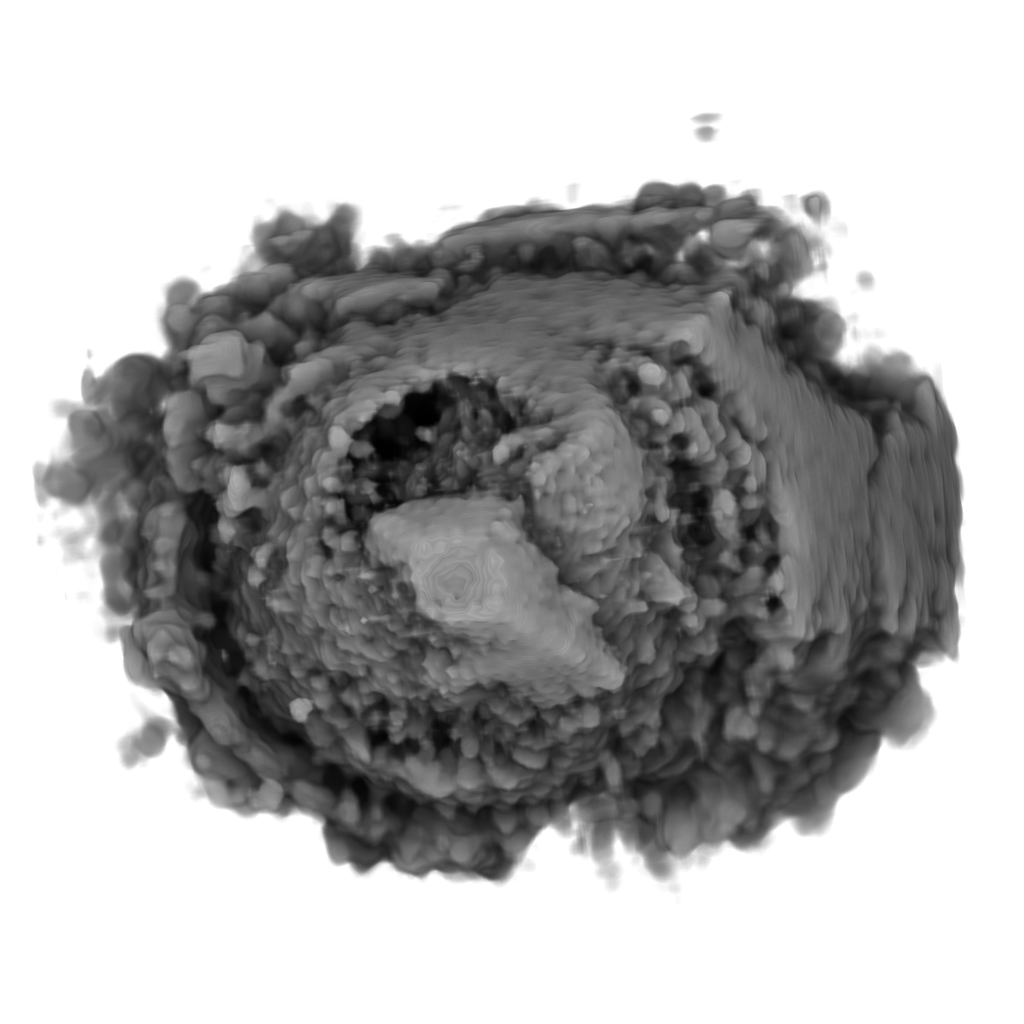

Recent works show that global illumination models based on gradient-free methods are suitable for rendering ultrasound volumes Ropinski10 ; solteszova10 . Ropinski et al. described a volumetric lighting model which simulates scattering and shadowing Ropinski10 . They use slice-based volume rendering from the view of the light source to calculate a light volume and raycasting to render the final image (see Figure 7b). A perceptual evaluation of the generated images indicates, that the proposed model yields stronger depth cues than gradient-based shading. Šoltészová et al. presented a single-pass method for simulation of light scattering in volumes solteszova10 . Light transport is approximated using a tilted cone-shaped function which leaves elliptic footprints in the opacity buffer during slice-based volume rendering. They use a slice-based renderer with an additional opacity buffer. This buffer is incrementally blurred with an elliptical kernel, and the algorithm generates a high-quality soft-shadowing effect (see Figure 7c). The light position and direction can be interactively modified. While these two techniques have been explicitly applied to 3D US data, the application of other volumetric illumination models potentially also improves the visual interpretation of 3D US data. Figure 8 shows a comparison of six different shading techniques as applied to a 3D US scan of a human heart. While the first row of Figure 8 shows examples for the already addressed shading techniques, the second row shows three alternative approaches. Figure 8d incorporates scattering of light in volume data, as proposed by Kniss et al. kniss02halfangle . Their slicing technique allows textured slices to be rendered from both light and viewing direction simultaneously. By sampling the incident light from multiple directions while updating the light’s attenuation map, they account for scattering effects in slice-based volume rendering. Figure 8e shows the application of the directional occlusion shading technique schott09directionalocclusion . This technique constrain the light source position to coincide with the view point. Finally, Figure 8f shows the application of a technique based on spherical harmonic lighting lindemann10materials .